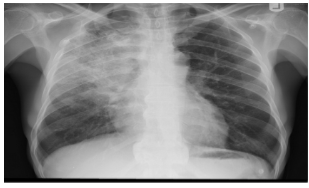

- AP chest film which shows opacification of the middle and lower zones of - (1 .the left lung. The upper border of the opacity is concave

- .This indicates pleural effusion (PE) - (2

- After inserting chest tube, pus was coming out. This means that the PE is - (3 .an Empyema

- .The cause of this empyema is most likely a Bacterial Pneumonia - (4

- The age of the patient is an 8 years which means that the most likely - (5 .organism is Streptococcus Pneumonae